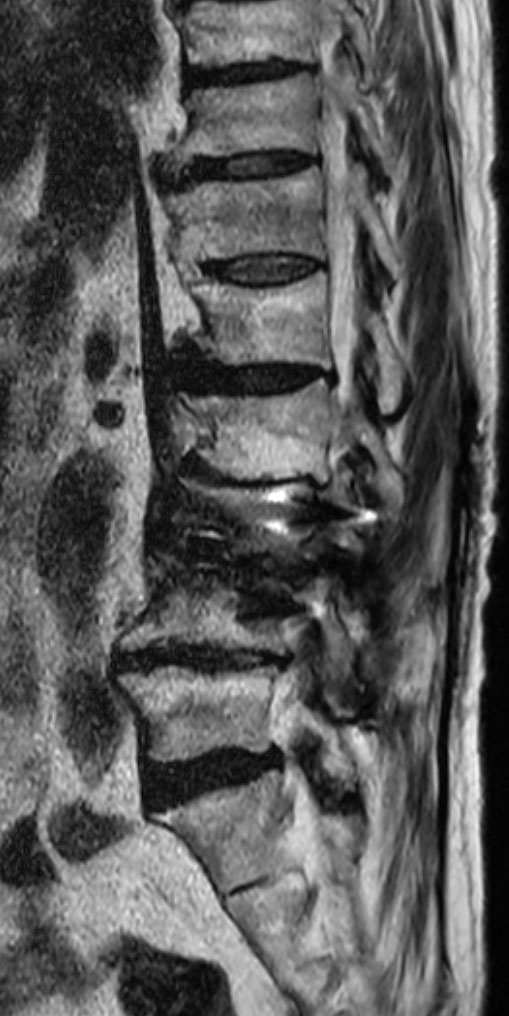

Sagittal T2w TSE